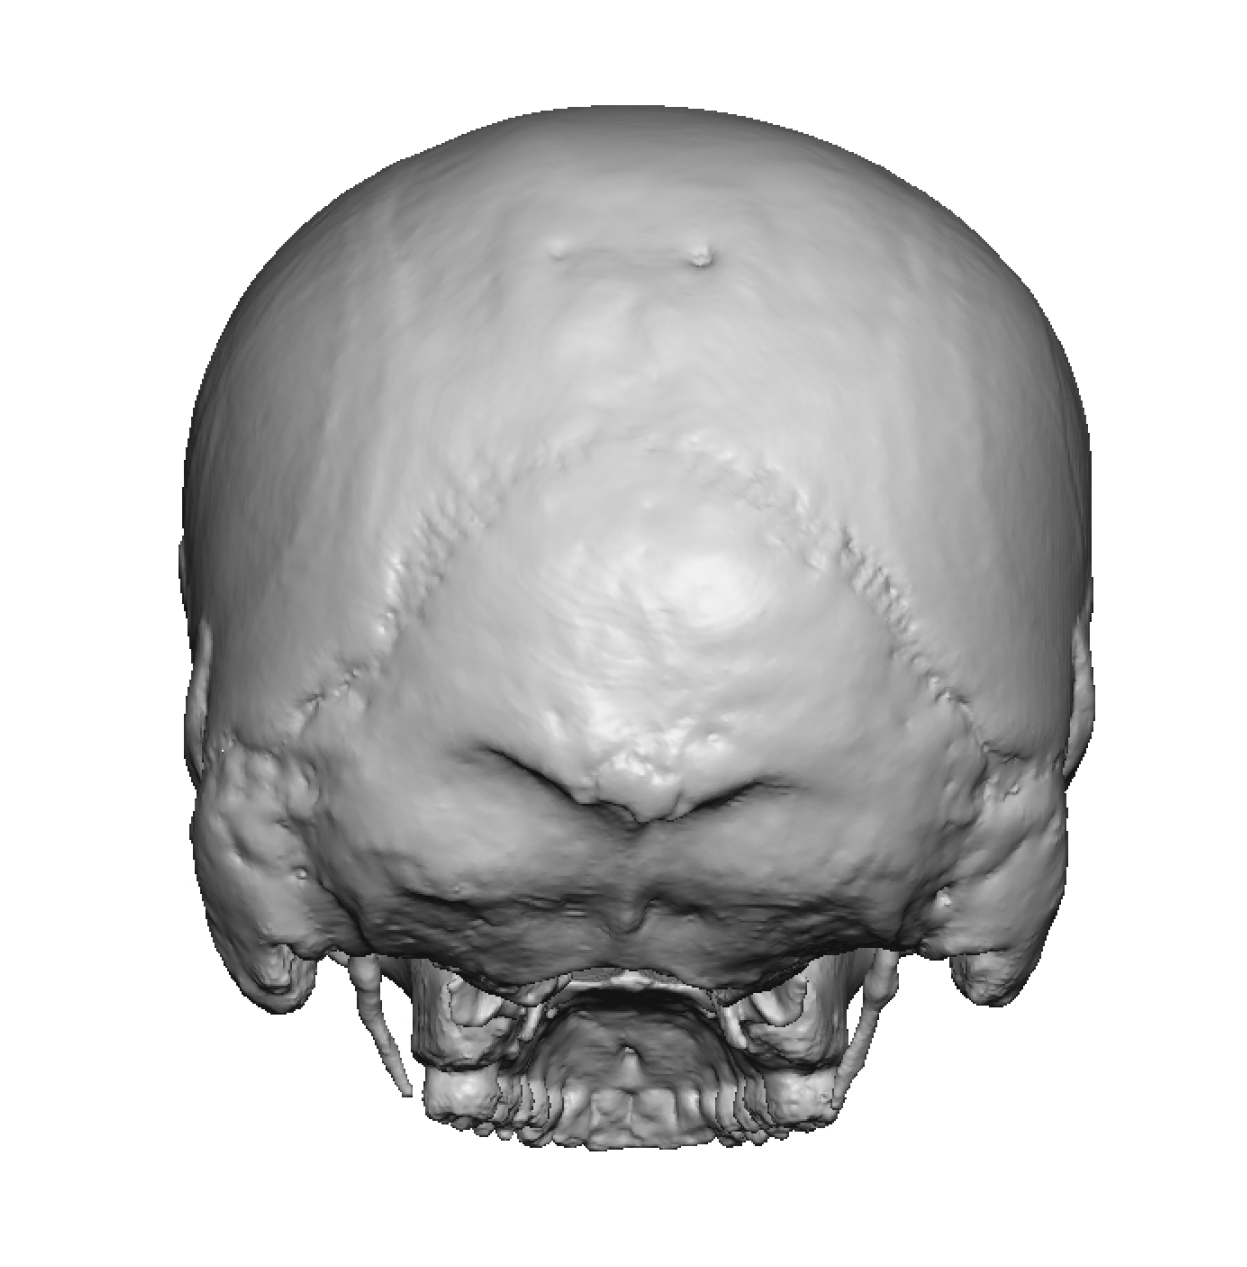

Patient 12

Desire to make her small head taller and wider.

Two stage skull augmentation using a first stage scalp expansion and a second stage custom skull implant for increased head height and shape.

Desire to make her small head taller and wider.

Two stage skull augmentation using a first stage scalp expansion and a second stage custom skull implant for increased head height and shape.